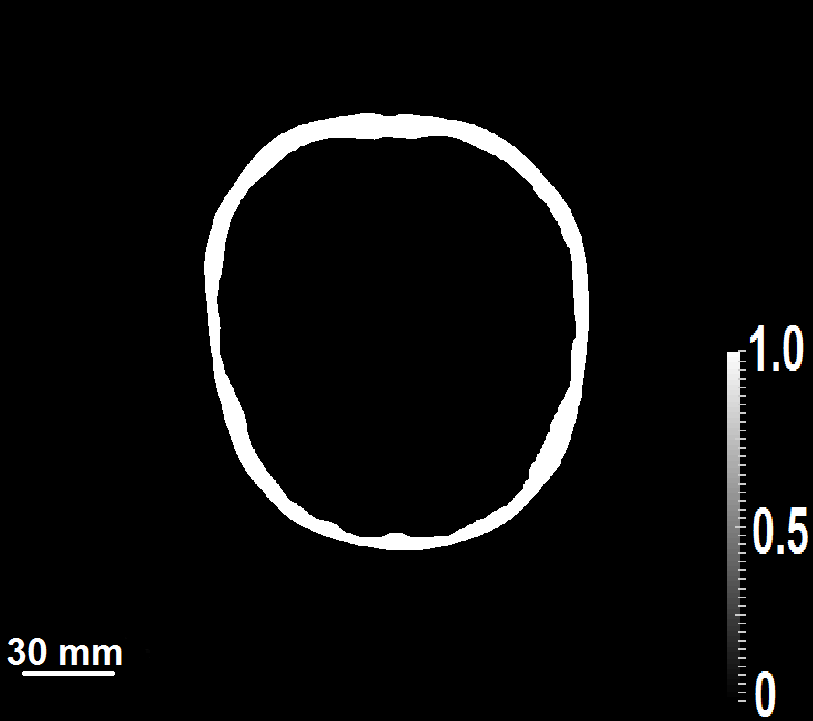

7.2 Experimental studies: Results

The images reconstructed from the experimental data are shown in  Fig. 8.  Figs. 8a, 8b and 8c displays the image reconstructed by application of superscript\mathbb{H}^{\dagger}, while the image reconstructed by use of the BP algorithm is shown in  Figs. 8d, 8e and 8f. In the BP reconstruction algorithm, the longitudinal speed of sound of the background fluid media was set to be 1.507 mmμsmm𝜇s\frac{\text{mm}}{\mu\text{s}}.

Figure 8: The reconstructed initial pressure distribution using superscript\mathbb{H}^{\dagger} along three different views are shown in (a)-(c).The reconstructed initial pressure distribution using BP algorithm along three different views are shown in (d)-(f).The reconstructed initial pressure distribution using μ=0superscriptsubscript𝜇0\mathbb{H}_{\mu=0}^{\dagger} along three different views are shown in (g) -(i).

These results demonstrate that the superscript\mathbb{H}^{\dagger} can more effectively mitigate image distortions due to acrylic globe (i.e., simulated skull structure) than can the BP algorithm. Additionally, some of the smaller vessel structures are not identifiable in the BP image but are present in the image reconstructed by use of superscript\mathbb{H}^{\dagger}.

The image reconstructed by use of μ=0subscriptsuperscript𝜇0\mathbb{H}^{\dagger}_{\mu=0} is shown in Figs. 8g, 8h and 8i. This image contains dramatically elevated artifact levels as compared to the one reconstructed by use of superscript\mathbb{H}^{\dagger}, shown in Figs. 8a, 8b and 8c. This again demonstrates that neglecting to model the elastic properties of the medium can lead to significant deterioration in image quality.